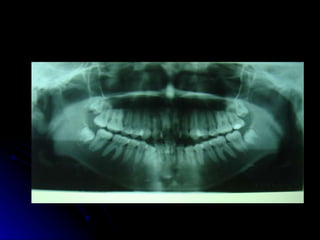

Plan de trabajo para el Diagnóstico X Interconsulta X Radiografía Lateral X Radiografías Panorámica X Modelos de Estudio X Fotografías Pz. 1.8, 2.8 germen en evolución extra ósea, 3.8, 4.8 germen en evolución extra ósea y mesioangulados, Incisivos inferiores extruidos. RESULTADOS

Plan de trabajopara el Diagnóstico X Interconsulta X Radiografía Lateral X Radiografías Panorámica X Modelos de Estudio X Fotografías Pz. 1.8, 2.8 germen en evolución extra ósea, 3.8, 4.8 germen en evolución extra ósea y mesioangulados, Incisivos inferiores extruidos. RESULTADOS